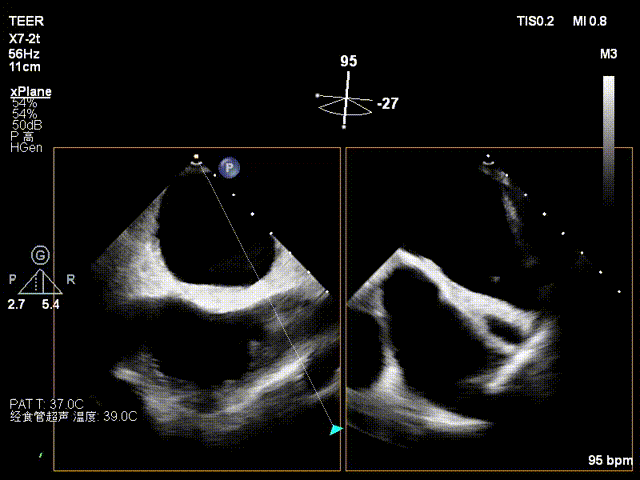

患者为73岁老年男性,经食道超声检查提示:急性二尖瓣腱索断裂合并反流,前叶长度:2.8cm,后叶长度:1.7cm,脱垂宽度:18mm,脱垂高度:8mm,瓣口面积:6.5cm²。

术前影像

左房极小

房间隔增厚

X-plane2区

X-plane2区彩色